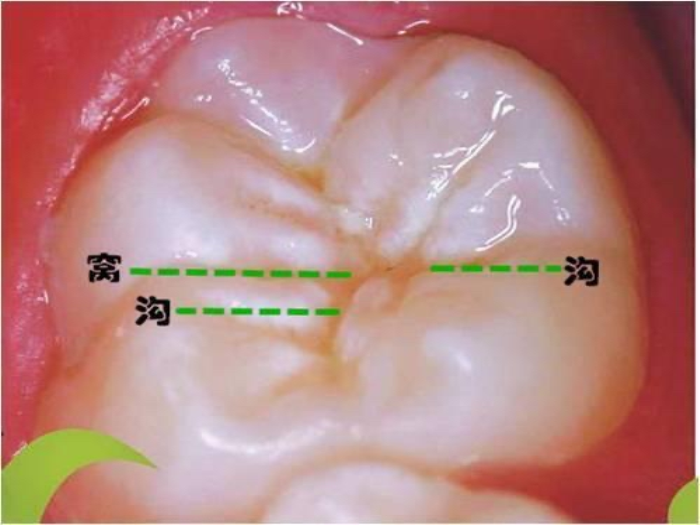

儿童牙齿做窝沟封闭比较合适的时间是牙齿完全萌出,或牙冠窝沟点隙均完全暴露于口腔,且龋齿尚未发生的时候。

一般乳磨牙在3-4岁,第一恒磨牙在6-7岁,第二恒磨牙在11-13岁为最适宜封闭的时候。不同儿童牙齿萌出的时间不一样,有的比较早,有的比较迟,建议根据具体情况调整进行窝沟封闭的年龄。